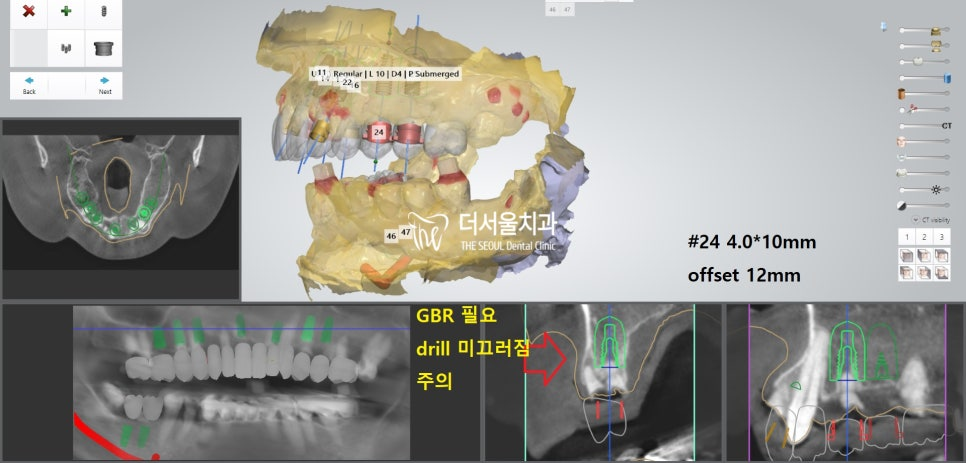

더서울에서 항상 했던 그대로

디지털 분석을 통해 인접치,

주변 조직과의 위치 관계를 파악했습니다.

계산된 위치에 맞춰 픽스쳐를 심어드렸습니다.

개수가 많기 때문에 걱정이 되었지만,

미리 제작된 가이드를 사용하여 수술을 진행하였더니

즉시식립 임플란트 과정을

정확하고 안전하게 끝마칠 수 있었습니다.